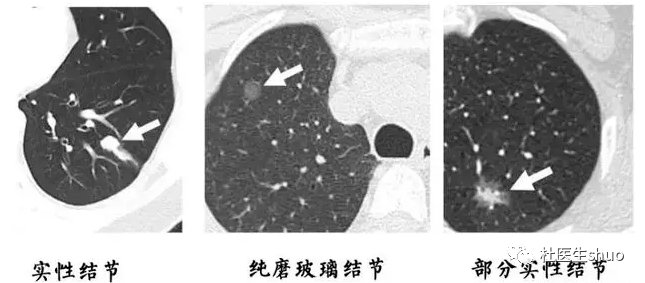

近年来,由于健康意识的提高和高分辨率CT(HRCT)的普及,肺结节的发现率明显上升。特别是在中国,肺部磨玻璃结节(GGN)的发现率有明显增加。肺部磨玻璃结节可能是肺部恶性肿瘤或良性病变的影像学表现。

首先,磨玻璃结节特别是纯磨玻璃结节几乎不会转移,因此多发的磨玻璃结节和转移是两回事。

其次,肿瘤的恶性程度及治疗效果由肺内最严重的一个病灶决定,跟病灶的个数没有关系,一个3厘米的混合性磨玻璃结节一定比10个5毫米大小的纯磨玻璃结节恶性程度高。